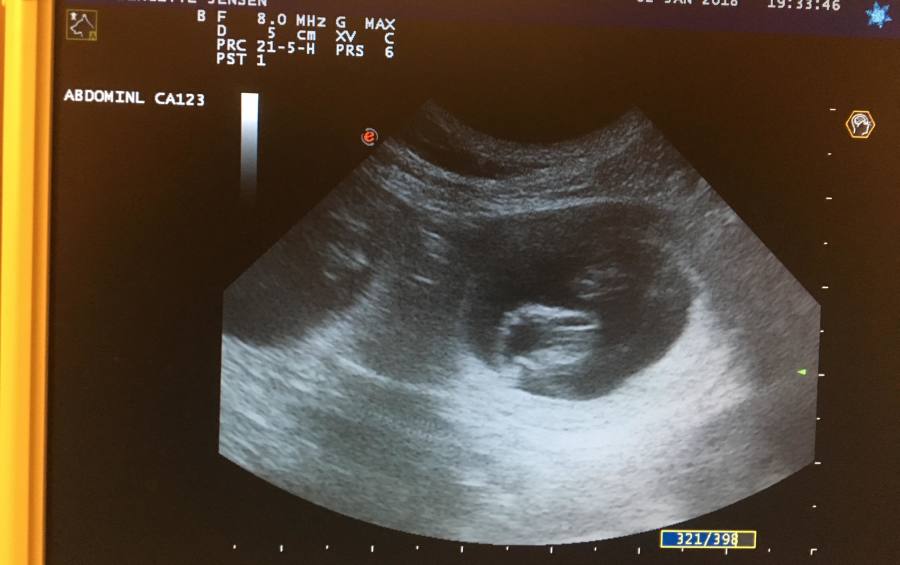

Enya (Skylock City Glam) has been to the vet today, to get a x-ray and ultrasound of her stomach and all the puppies inside.

We choose to do so because of Enya's safty when giving birth and to get a more correct idea of the number of puppies we should expect during birth.

As you can see they're quite packed and there's still a while before the start of February and the arrival of the puppies!

Take a look and see how many puppies you can count :-)